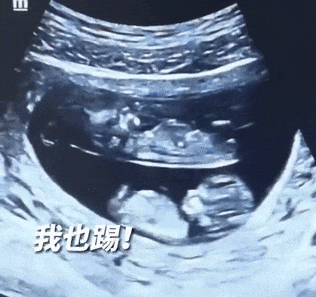

近日,一对还未出生的双胞胎宝宝火爆全网,有网友晒出了他们的B超照,十分有趣。

视频中

两个宝宝在母亲的肚子里

呈上下分布

并且还不停踢动

对此网友评论调侃

"原来双胞胎还有'上下铺'啊!"

双胞胎"分房"的形态

大多不太规整

"一般来说,双胞胎最常见的是'双绒双羊'。"湖北省妇幼保健院超声诊断科副主任朱霞解释,也就是子宫内有两个绒膜、两个羊膜腔,好比两个胎儿各住一套房,独门独户互不干涉。